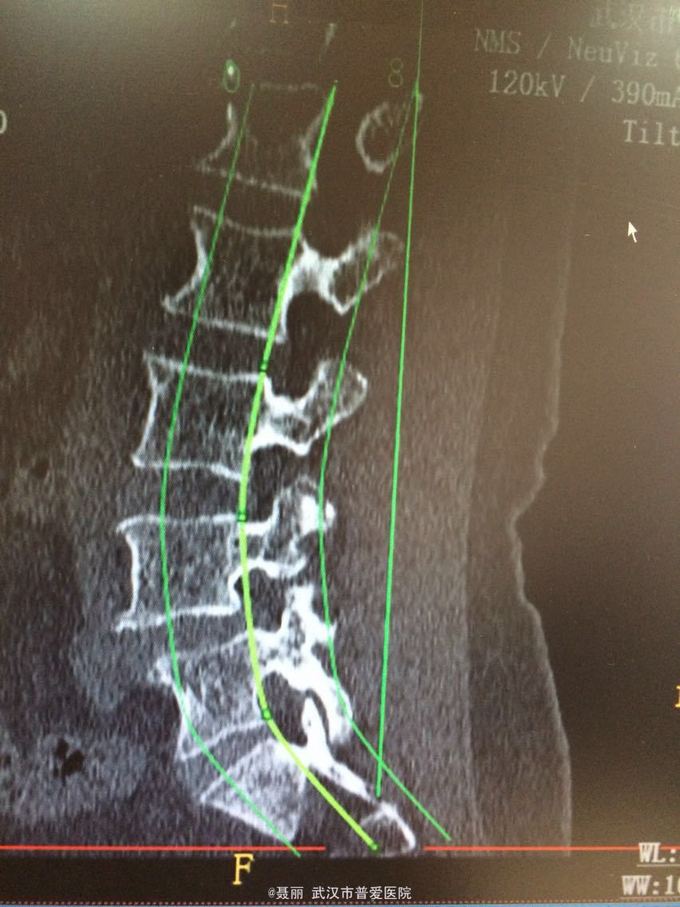

患者,女,61岁 因腰部疼痛,伴左下肢酸胀、疼痛、麻木5月余入院。 患者约5月前无明显外伤等诱因感腰腿疼痛不适,以腰部及左下肢为主,活动后左下肢疼痛加重,休息可缓解。 既往病史:既往体健,否认高血压、糖尿病等其他传染病史,否认食物药物过敏史。

辅助检查:2015年2月27号到我院拍腰椎MRI检查提示:L4椎体Ⅰ-Ⅱ度滑脱,腰椎退变。

初步诊断:腰椎滑脱症 治疗计划:1、完善相关检查:胸片、心电图,血常规,尿常规,肝肾功能电解质、术前全套 2,活血化瘀扩管治疗。卧床休息。 L4滑脱复位+L4/5椎间盘摘除、椎管减压+椎间cage3植骨融合术